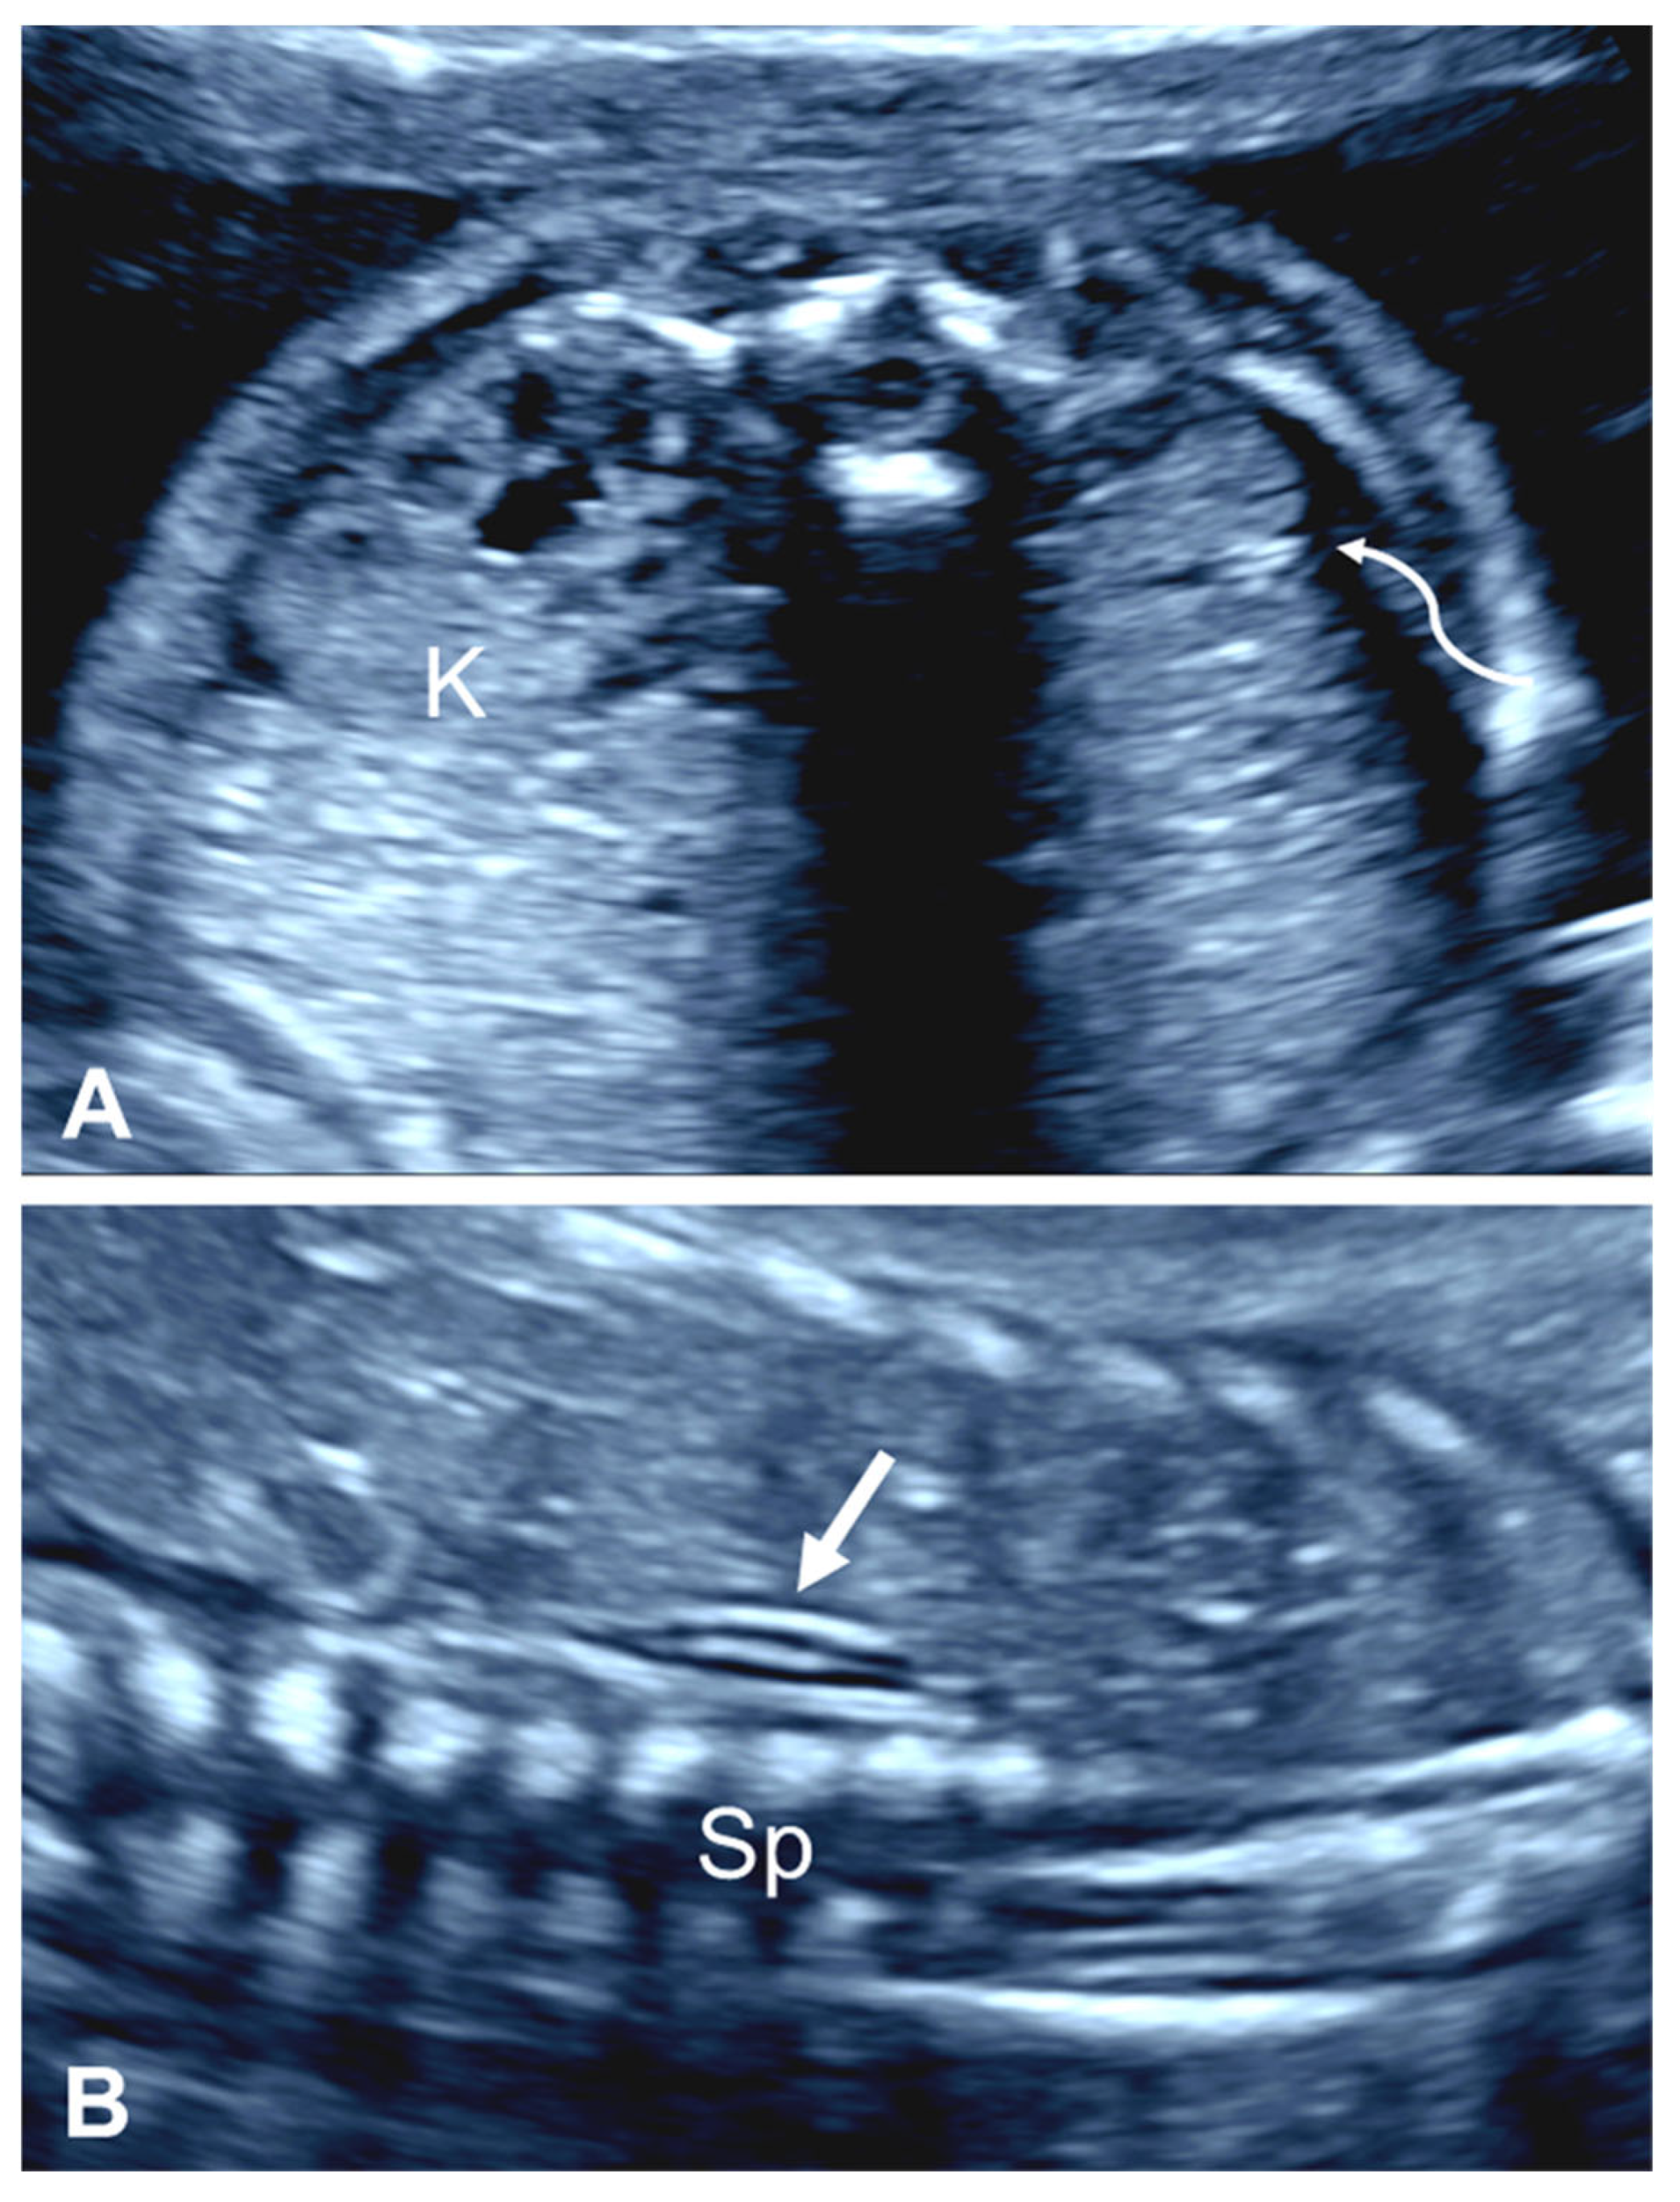

2.2.2. ‘Lying Down’ Adrenal Gland

2.2.3. Contralateral Renal Hypertrophy

2.2.4. Absent Ipsilateral Renal Artery